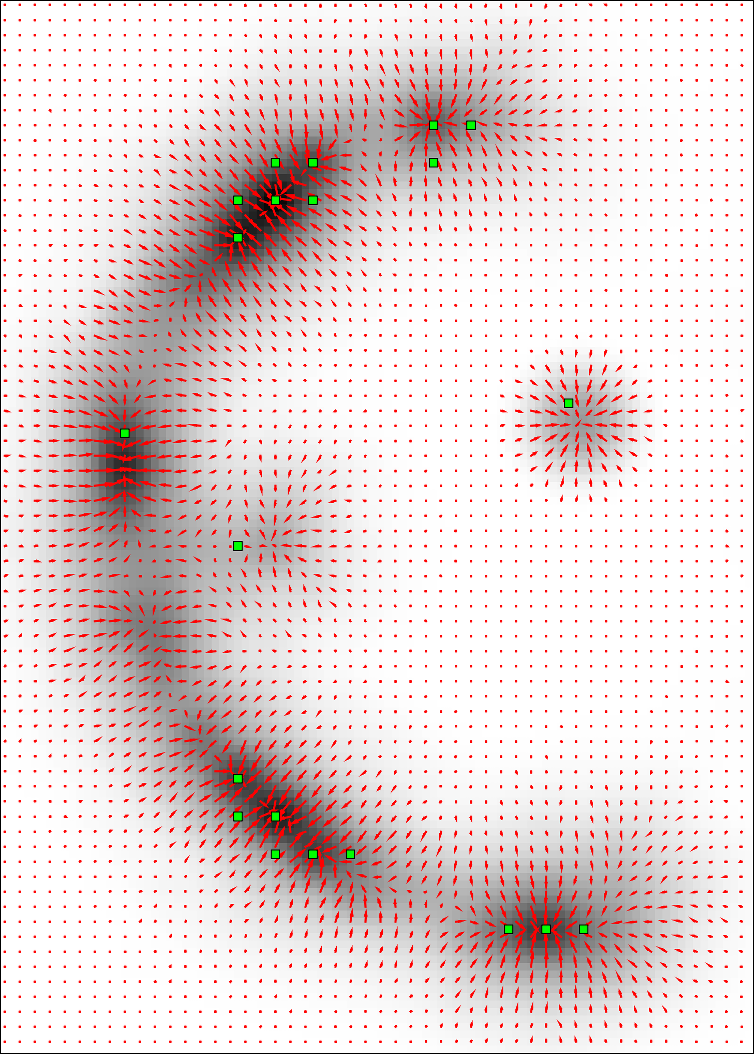

, , and modulate the respective components of the canonical Laplacian of Gaussian () filter oriented along the principal directions of . It is clear that given any arbitrary orientation as an orthonormal basis similar to , the proposed dictionary of filtering kernels can steer by computing the rotation transform, which maps the integral orientation basis of each Gaussian kernel on . Together with the SLoGS filtering kernel , we determine the second-moment matrix associated to the filter impulse response by adopting the ellipsoid model in the continuous neighborhood of . A symmetric tensor is derived from the eigendecomposition of as , where is the diagonal matrix representing the canonical unitary volume ellipsoid

the respective semiaxes’ lengths. Conversely from , which is indeterminate, the tensor field is a symmetric positive definite (SPD) matrix for any . Here, the definition of the tensor kernel in (4) can be further reformulated exploiting the intrinsic log-concavity of . By mapping , a convex quadratic form is obtained, so that is an SPD, as the modelled tensor . In either case, the manifold of tensors can be mapped into a set of 6 independent components in the Log-Euclidean space, which greatly simplifies the computation of Riemannian metrics and statistics. We refer to [3] for a detailed methodological description. The continuous and smooth tensor field inherits the steerable property. Similarly to diffusion tensor MRI, the kernel shows a preferred diffusion direction for a given energy potential, e.g. the scalar function itself (fig. 1). This allows to define an arbitrary dictionary of filtering kernels (DFK) that embeds anisotropy and high-order directional features to scalar curvilinear templates, which enhances and locally resembles typical, smooth vessel patterns. Together with the arbitrary SLoGS DFK, we also introduce an extra pair of non-curvilinear kernels for completeness. These are the pseudo-impulsive , an isotropic derivative filter given by the Laplacian of Gaussian of , representing a Dirac delta function for . Also, the uniformly flat is another isotropic degenerate case, where the Laplacian of Gaussian derives from , which is assumed to be a uniform, constant-value kernel for . The purpose of introducing the extra kernels is to better contrast regions that most likely relate to vessel boundaries and to image background, respectively. Although and have singularities, ideally they represent isotropic degenerate kernels. Therefore we associate pure isotropic tensors for any given , so that (Identity). The respective directional kernel bases are undetermined.

where is the integral normalizing weight-map accounting for all vessel, boundary and background components; is the modulating SLoGS filter response at as in (7); is the steered Gaussian impulse response associated to the kernel ; is the Hann smoothing window in the neighbourhood centred at , and is one of the 6 components of the discrete steered tensors patch in the Log-Euclidean space. Note that all 6 tensorial components are equally processed, and that the neighbourhood and the SLoGS tensors patch have the same size. In (8), integrates also the isotropic contributions from vessel boundaries and background to better contrast the tubular structures’ anisotropy and to reduce synthetic artifacts surrounding the vessels (fig. 1). In particular, is averaged with an identically null tensor patch in the Log-Euclidean space in correspondence of boundaries and background, and is computed as in (7), where the image negative of is considered. Lastly, the connected vesselness maps and the associated synthetic tensor field are reconstructed by adding adjacent overlapping blocks in the OLA 3D grid for the given scale .

The scalar vesselness responses of both HCP and PC images are determined using the state-of-the-art Frangi filter (FFR) [8], and Optimally Oriented Flux (OOF) [12]. Also, the connected vesselness map (CVM) and the associated tensor field (TF) are synthesized for the same dataset using VTrails. The connectedness of the considered scalar maps is qualitatively assessed and the TF is inspected as proof of concept in section 3.1.

Fig. 3 shows the connectedness of vessels recovered from state-of-the-art vascular enhancers and curvilinear ridge detectors FFR and OOF together with the proposed CVM for the synthetic HCP and the real PC images.

On the synthetic phantom, FFR shows a fragmented and rough vesselness response in correspondence of irregularly shaped sections of the structure. Also, the response at the bifurcation is not smoothly connected with the branches (triangular loop). Conversely, OOF recovers the phantom connectedness at the branch-point, and the vesselness response is consistent along the tortuous curvilinear section, however ghosting artifacts are observed as the shape of the phantom becomes irregular (C-like) or differs from a cylindrical tube. Also, close convoluted structures, which change scale rapidly in the HCP, produce inconsistent responses of OOF (fig. 3). CVM shows here a strongly connected vesselness response in correspondence of both regular and irregular tubular sections, with local maxima at structures’ mid-line. The connectedness of the structures is emphasized regardless the complexity of the shape, and it resolves spatially the tortuous curvilinear ‘kissing vessels’ without additional ghosting artifacts, despite the smooth profile.

Similar results are observed on the PC dataset: FFR has a poor connected response in the noisy and low-resolution image. Vessels are overall enhanced, however thin and fragmented structures remain disconnected. Overall, the vesselness response is not uniform within the noisy structures, where maximal values are often off-centred. A more consistent response is obtained from OOF, where the connectedness of vessels is improved. Maximal response is observed at the mid-line of vessels, however, noise rejection is poor. CVM strongly enhances here the vessel connectivity. The fragmented vessels of PC have a continuous and smooth response in CVM with higher values and a more defined profile. Large vessels shows solid connected regions with local maxima at mid-line as in OOF. Conversely from OOF, CVM shows improved noise rejection in the background.

The respective tensor fields (TF) synthesized on both HCP and PC show consistent features. The TF’s characteristics are in line with the connectedness of CVM: enhanced and connected vessels are associated with high anisotropy, whereas background areas show a predominant isotropic component.